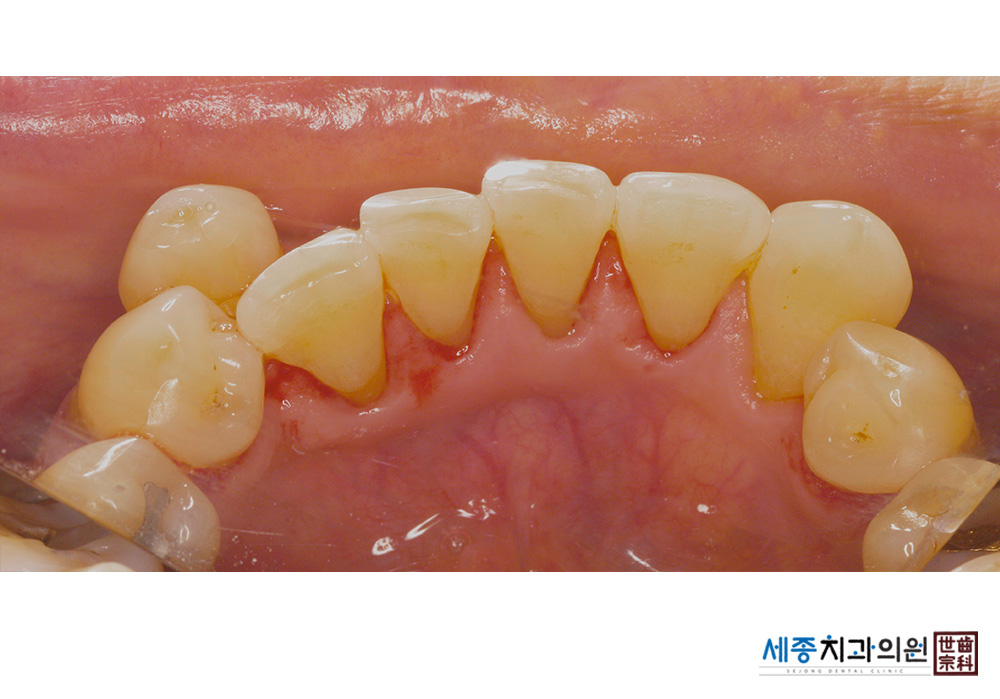

[스케일링] 치주질환 예방 스케일링

치료전 : 2021-01-20

치료후 : 2021-01-20

가글마취&저주파 스켈러를 사용한 스케일링